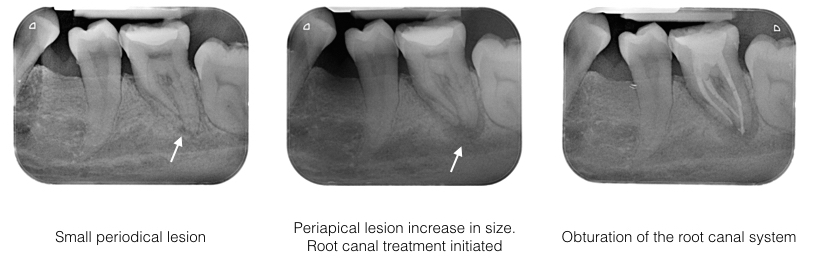

Examination: Tooth 36 has a large restoration. The tooth is mildly tender to percussion and not resposive to cold test. Radiograph showed the tooth with a small periapical lesion. Since the tooth does not cause much trouble at the time of examination, patient requested, to observe the condition further.

6 months later, the pain on the lower left 1st molar returns and the radiograpgh showed the periapical lesion has increased in size. Tooth was very tender to touch.

Diagnosis: Acute apical periodontitis of tooth 36

Treatment: Root canal treatment was carried out on tooth 36 under rubber dam isolation. Both mesial canals are curve. All 3 canals were cleaned and shaped. Calcium hydroxide dressing were placed for disinfection. One week review showed tooth 36 is no longer painful. Obturation was carried out on all the 3 canals.